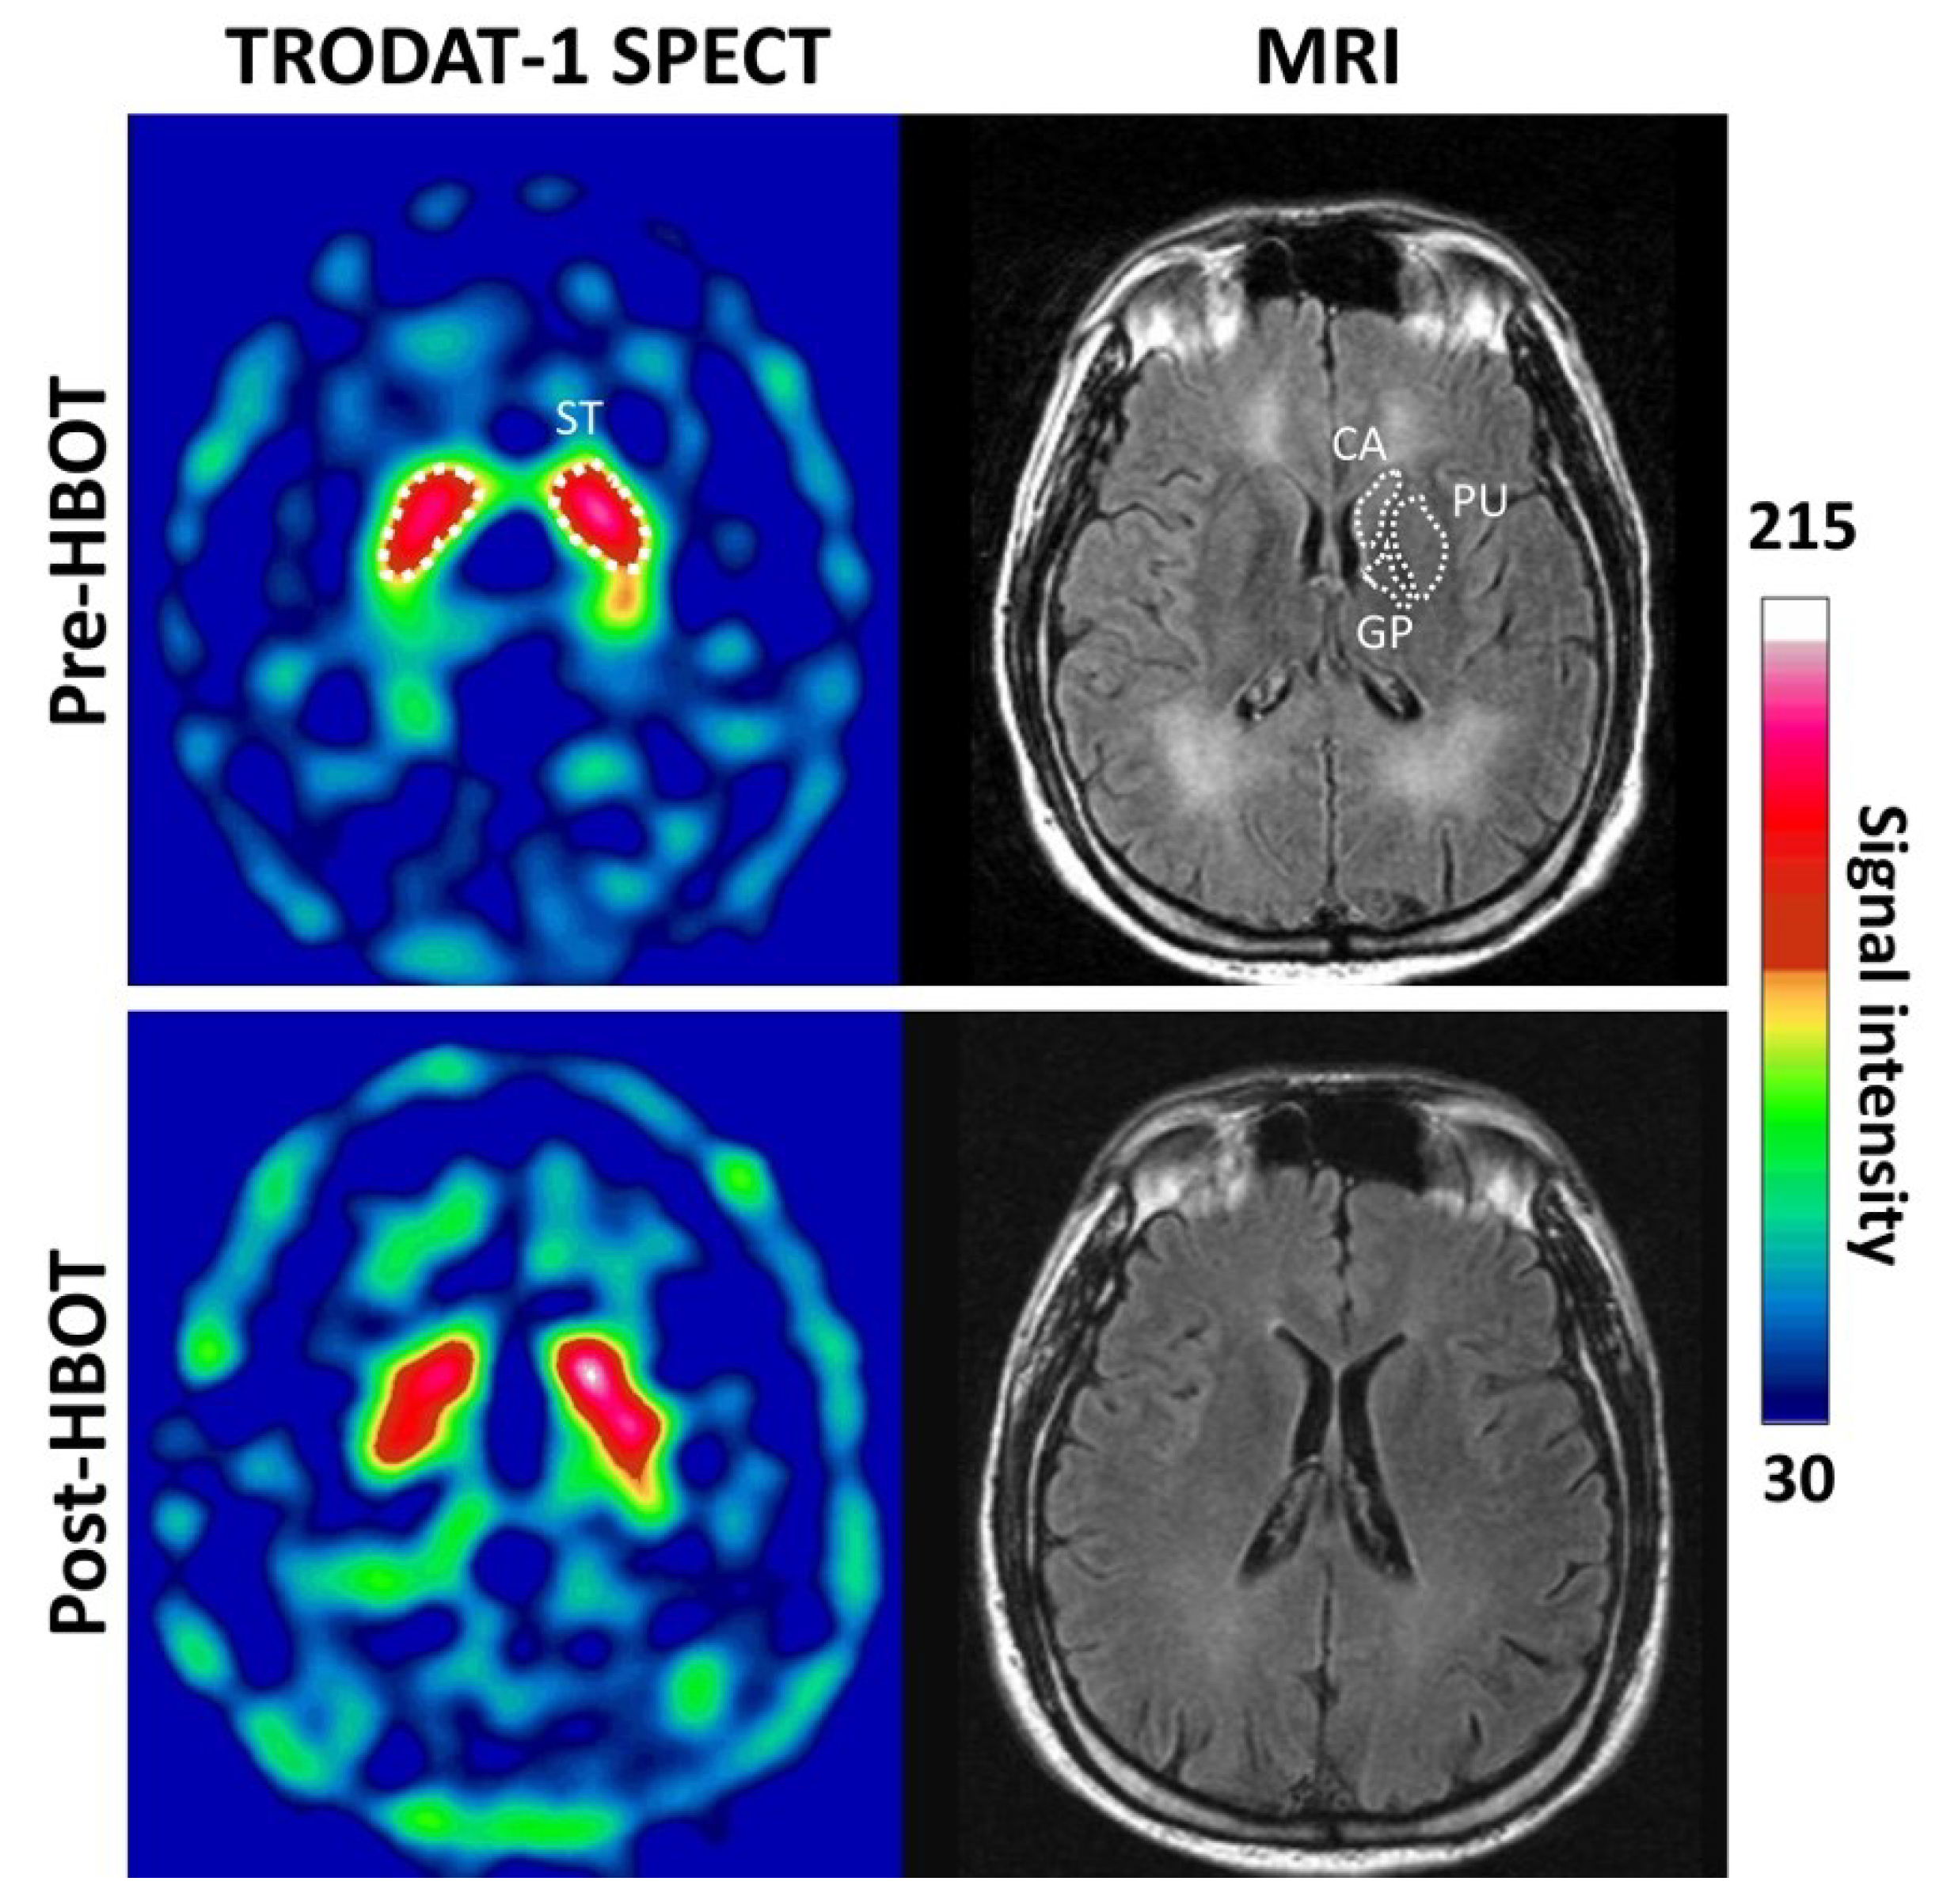

3.2. 99mTC-TRODAT-1 SPECT DAT Availability Is Significantly Reduced in Parkinsonism Syndrome and HBOT Has Limited Effects

Figure 3 shows example Tc-99m-TRODAT-1 SPECT images of the striatal region of a 33-year-old female subject with non-Parkinsonian syndrome and a 35-year-old male subject with Parkinsonism syndrome at baseline and 3-month follow-up. No significant visible increases in 99mTC-TRODAT-1 SPECT signals were observed in the non-Parkinsonian or Parkinsonian subjects at 3 months after HBOT.

Figure 3. Example transverse 99mTc-TRODAT-1 DAT SPECT and MR images of the striatal regions of patients with non-Parkinsonian and Parkinsonian syndrome before and after HBOT. A 33-year-old female subject with non-parkinsonian syndrome and a 35-year-old male subject with parkinsonism syndrome exhibited similar DAT availability before (baseline) and after HBOT 3-month follow-up, respectively.